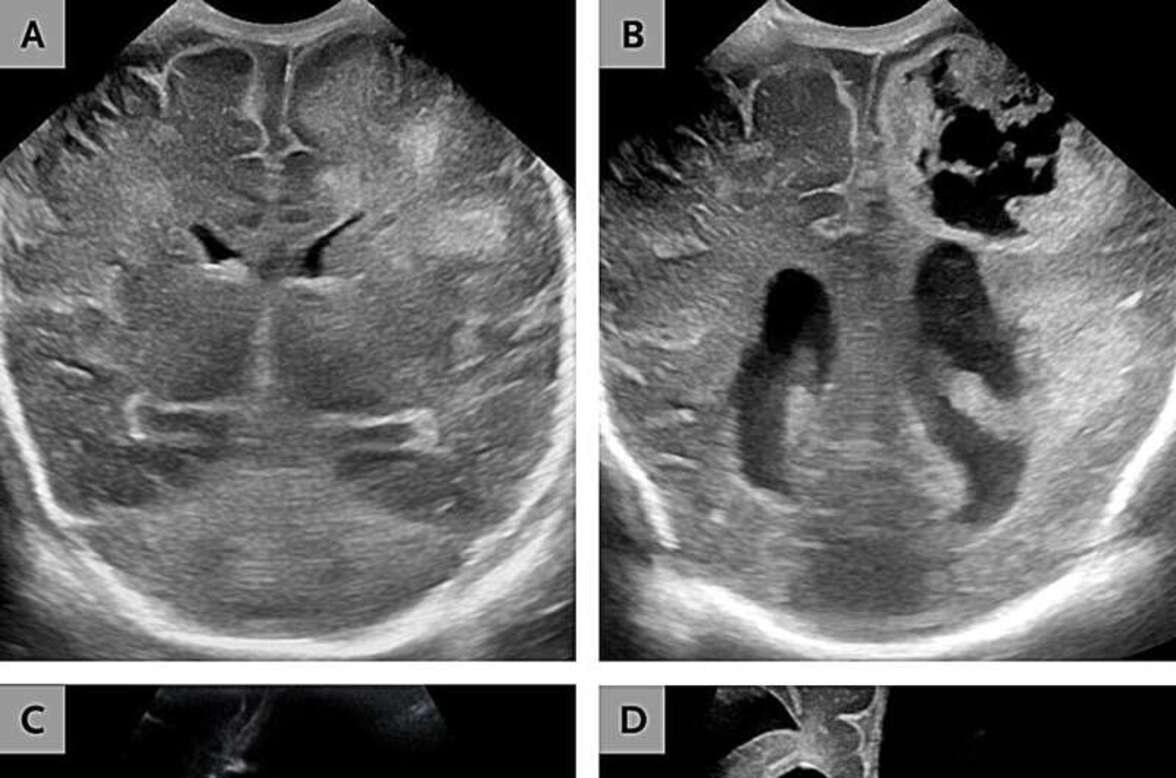

В одном случае речь шла о двухмесячной девочке, родившейся на сроке беременности 26 недель. В посевах крови и спинномозговой жидкости были обнаружены бактерии Paenibacillus thiaminolyticus, но никаких других патогенов обнаружено не было. Томография головного мозга выявила прогрессирующую гидроцефалию, энцефаломаляцию и образование абсцессов, что потребовало установки шунта.

Второй новорожденный появился на свет в возрасте 37 дней после преждевременных родов на сроке 33 недели беременности. Сложности с кормлением и отсутствие реакции привели к госпитализации. В посевах крови и спинномозговой жидкости снова были обнаружены P. thiaminolyticus, а на снимках был выявлен разжижающий менингоэнцефалит, при котором ткань мозга начинает превращаться в вязкую жидкость. Терапия включала внутривенное введение ампициллина и установку шунта. Клиническое ухудшение прогрессировало до трудностей с кормлением и судорог, кульминацией которых стала смерть в возрасте 11 месяцев.